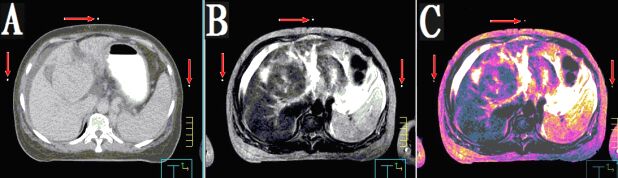

本產(chǎn)品主要適用于不同模態(tài)圖像引導(dǎo)下放療時定位,定點經(jīng)皮穿刺活檢或積液抽吸引流,不同模態(tài)間圖像融合控制點配準(zhǔn)等。

2.??多角度掃描小球,圖像均為高亮度圓點狀,無放置角度限制。

3.??同一定位貼,在多種模態(tài)掃描下成像均能顯示為點狀,可用作圖像融合的共同配準(zhǔn)控制點,大小、位置一致,方便全身或軀段臟器異機圖像融合,精度高,易開展新的臨床應(yīng)用。

CT和MR通用型:具有同一個定位球在CT掃描高密度、MR常規(guī)掃描高信號的特點,主要用于

CT/MR圖像融合,更換掃描設(shè)備,不需要更換標(biāo)記點。型號MK⊙CT/MR,每盒三貼;